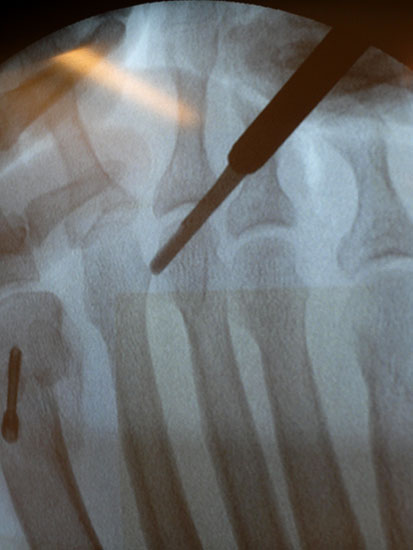

Nach Bestimmung der korrekten Osteotomiehöhe wird mit dem MIS-Mikrotom eine je nach Seitendominanz des Operateurs dorsolaterale oder dorsomediale 3-4mm lange Längsinzision parallel zu den Strecksehnen auf Höhe des metadiaphysären Überganges am distalen, zu osteotomierenden Metatarsale  durchgeführt. Im Anschluss erfolgt die Präparation mit einer schlanken, im Schaft gebogenen und vorne stumpfen Raspel oder mit einem gebogenen Klemmchen. Die Präparation erfolgt unter stetigem  Knochenkontakt mit der Kortikalis des Metatarsale medial oder lateral bis nach plantar unter die Beugesehenen.  So kann der Weg für die Fräse vorpräpariert und eine Weichteilinterposition zwischen Fräse und Knochen vermieden  werden.

Jetzt erfolgt das Einbringen der Fräse im 45°-Winkel von distal dorsal nach proximal plantar. Auf steten Knochenkontakt mit der Kortikalis zur Vermeidung eines Weichteilinterponates sollte geachtet werden. In unserer Abteilung erfolgt vor Beginn der Osteotomie nun eine nochmalige Lagekontrolle der Fräse unter dem Bildwandler im dorsoplantaren Strahlengang. Eine zusätzliche laterale Aufnahme kann die Tiefe der eingebrachten Fräse in Bezug auf das zu osteomierende Metatarsale zeigen, ebenso ermöglicht sie eine Kontrolle des 45°-Winkels.

In einer rotatorischen Bewegung mit dem Drehpunkt im Bereich der Hautinzision erfolgt nun die Osteotomie zunächst - in Abhängigkeit von der zu operierenden Seite und der Rechts- oder Linkshändigkeit des Operateurs  - des medialen bzw. lateralen Kortex des Metatarsale, gefolgt von den plantaren Anteilen und anschliessend dem gegenseitigen Kortex. Am Ende der rotatorischen Bewegung befindet sich die Fräse, die am Anfang der Osteotomie noch parallel zum Metatarsaleschaft ausgerichtet war, im 90°-Winkel zu diesem.